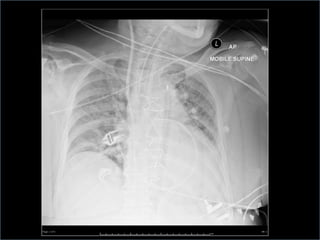

Confirmation of position

 arterial balloon waveform and pressures shown

 Chest x-ray or fluoroscopy

radiopaque tip lies in the 2nd intercostal spaces

just above the left main bronchus; lower end of

balloon should lie cephalad to the renal arteries